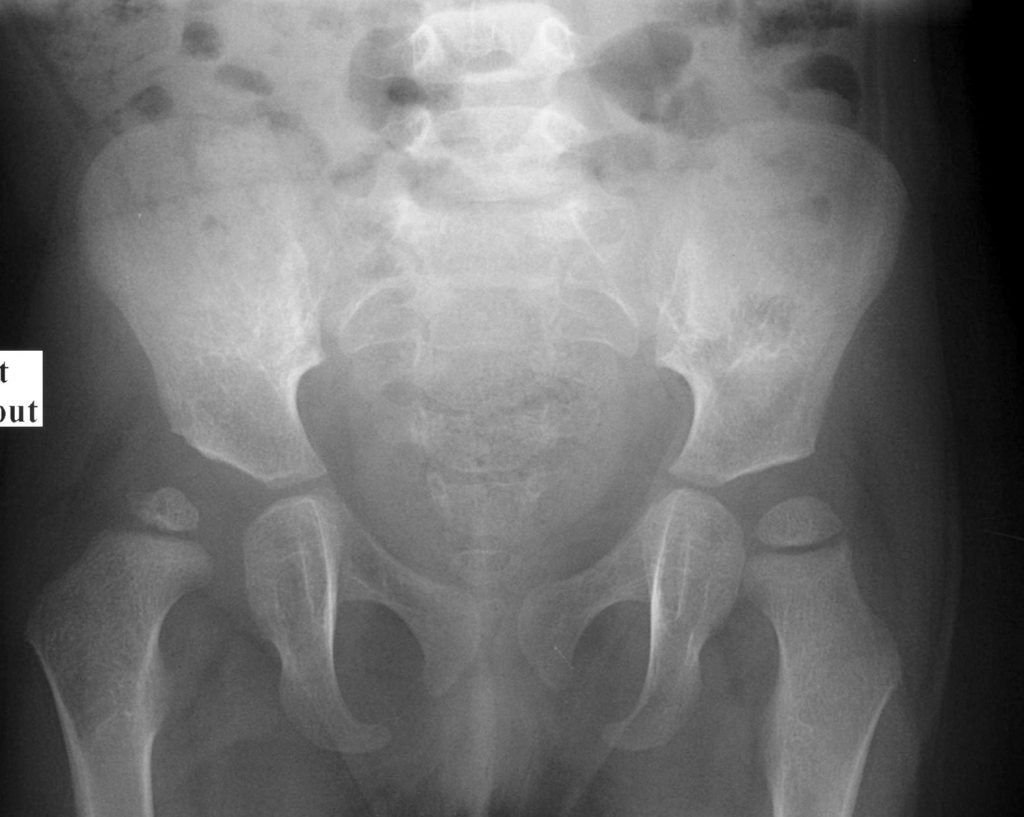

La radiographie du bassin n’est plus un examen de dépistage. Elle est utile à partir de l’âge de 4 mois pour visualiser les hanches dans le suivi d’une échographie pathologique ou en cas de doute clinique (figure 116.3).

Fig. 116.3 Surveillance radiographique à distance d’un enfant de 2 ans diagnostiqué pour dysplasie de hanche.

Le toit du cotyle droit comparativement au côté gauche est mal creusé, verticalisé et moins condensé, conséquence de l’excentration de la tête fémorale. Le noyau de la tête fémorale droite est moins ossifié que le gauche, témoin de l’asymétrie de charge sur ces deux structures.

Source : CERF, CNEBMN, 2022.